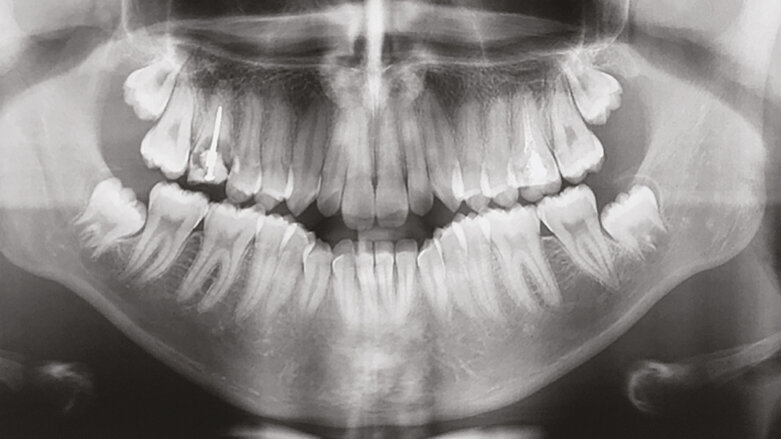

RTG vyšetření předlolženého případu (fotografie: Gianluigi Fiorillo, DDS)

Prezentovaný případ je šestnáctiletý chlapec se skeletální II. třídou a dentální I. třídou. Intraorální klinický popis zahrnuje stěsnání, protruzi řezáků, pozitivní incizální schůdek i překus, horní první moláry se špatným biologickým faktorem a, v extraorálním aspektu, s inkompetentním retním uzávěrem a distální pozicí brady (obr. 1a–i). Prostorová analýza a vyhodnocení profilu vedly k indikaci extrakčního ošetření a navzdory počáteční úvaze o extrakci čtyř prvních premolárů bylo posléze rozhodnuto o extrakci prvních horních molárů a první dolních premolárů. Tento terapeutický plán vyžaduje věnovat velkou pozornost kotvení, a proto bylo stanoveno, že dva TAD budou použity v bukální oblasti meziálně u druhých horních molárů.